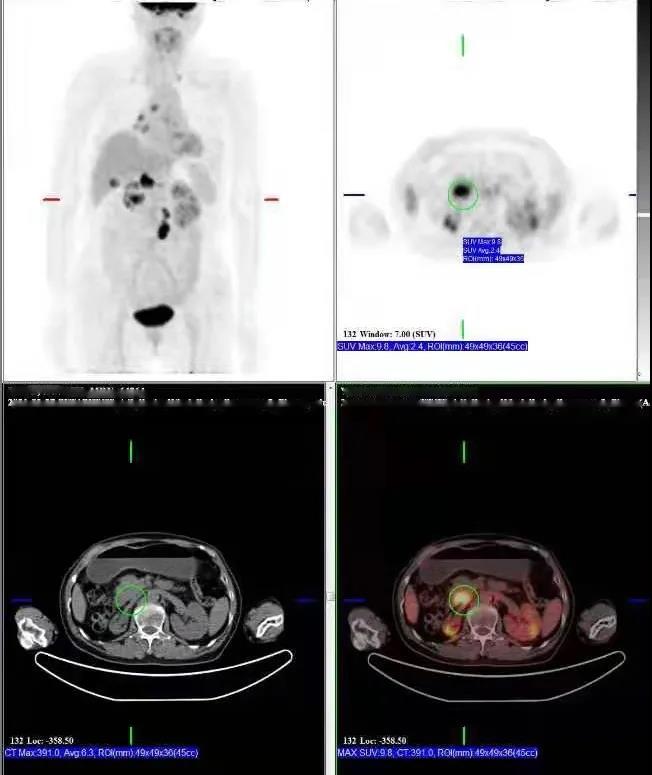

PET/CT檢查所見(jiàn):胰腺鉤突見(jiàn)一低密度灶,動(dòng)脈期及靜脈期強(qiáng)化稍低于周圍正常胰腺組織,延遲期掃描病灶與正常胰腺呈等密度,病灶邊界欠清晰,大小約2.6×3.7cm,F(xiàn)DG攝取增高,SUVmax:9.8。胰周脂肪間隙清晰,胰管未見(jiàn)擴(kuò)張。肝門區(qū)及腹膜后見(jiàn)多發(fā)腫大淋巴結(jié)影,增強(qiáng)掃描呈環(huán)形強(qiáng)化,最大者大小約2.2×3.5cm,F(xiàn)DG攝取增高,SUVmax:17.0。膽總管明顯擴(kuò)張,呈囊狀改變,最寬處約直徑4.5cm。

提示: 胰腺鉤突病變,糖代謝增高,考慮胰腺癌可能性大

肝門區(qū)及腹膜后淋巴結(jié),糖代謝增高,考慮轉(zhuǎn)移性淋巴結(jié)

先天性膽管擴(kuò)張